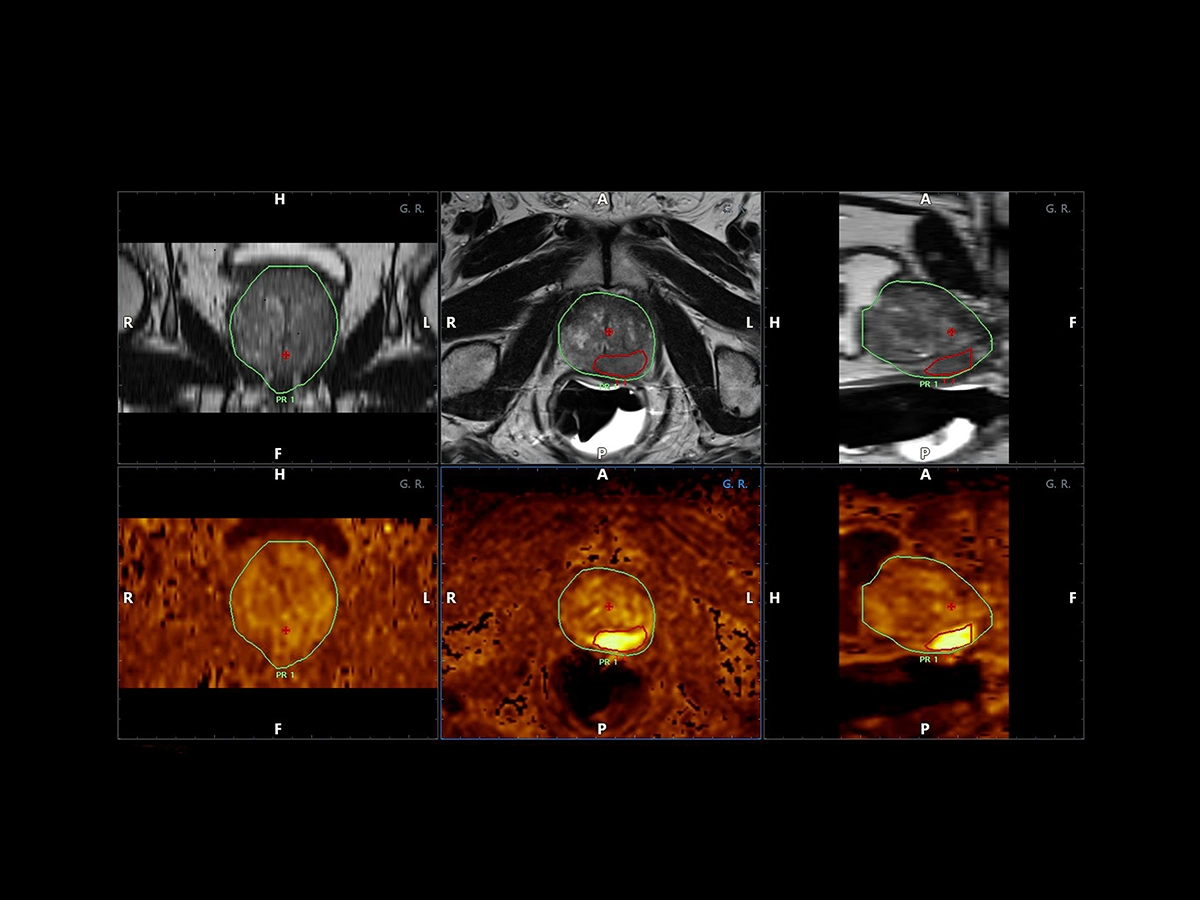

Expert users and beginners can now achieve a heightened degree of simplicity and precision by using UroFusion, Esaote’s cutting-edge fusion imaging solution that makes the most of the combination of US and MR or PET modalities.

By harnessing Augmented Insight™ (A.I.) technology, our dedicated solution enhances workflow efficiency by Automating MR Prostate Contouring & Segmentation with instant and automatic US-MR Synchronization, applied to both transperineal (TPUS) and transrectal (TRUS) prostate biopsy approaches.

Using UroFusion, clinicians will benefit from our intuitive tools to fasten the fusion procedures: the automatic prostate contouring and biopsy sample mapping are certainly the most impressive.

UroFusion seamlessly offers the ability to combine different mpMRI series, facilitating the identification of suspicious prostate lesions.

mpMRI targeting phase of PI-RADS 5 peripheral lesion